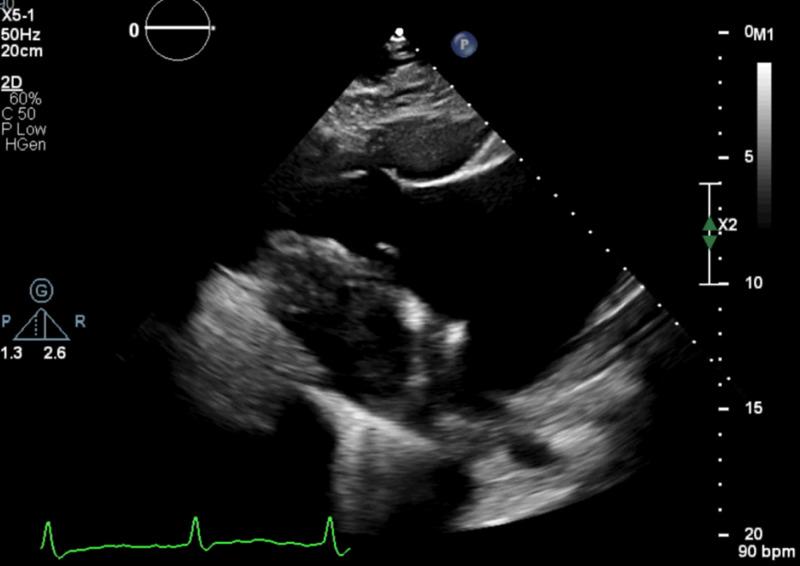

Ebstein's anomaly is a congenital defect, which is rarely present in adults with arrhythmias and right heart failure with tricuspid regurgitation. The diagnosis is made by non-invasive cardiac imaging with transthoracic echocardiography or cardiac magnetic resonance imaging. However, mild and atypical anatomical variants require a more specific investigation to make the diagnosis and differentiate it from other pathologies which have a similar presentation, including Arrhythmogenic Right Ventricular Cardiomyopathy (ARVC). We present the case of a 66-year-old gentleman with a history of recurrent admissions due to decompensated heart failure exacerbations, now presenting with gradually worsening dyspnea. An echocardiogram was obtained, showing a thin-walled, dilated, and dysfunctional right ventricle (RV) with severe tricuspid regurgitation due to poor coaptation of the tricuspid leaflets. Although a very distinctive epsilon wave was seen on his electrocardiogram, highly suggestive of arrhythmogenic RV cardiomyopathy (ARVC), which would be enough to explain his presentation and initial echocardiogram; an off-axis plane of the tricuspid valve without any RV aneurysm or dilation of the RV outflow tract was incongruent with this diagnosis. Additional echocardiographic images were determinant to demonstrate both apical displacement and tethering of the septal tricuspid leaflet with an abnormally long anterior tricuspid leaflet, suggestive of Ebstein's anomaly. This diagnosis was confirmed with cardiac magnetic resonance imaging. Mild variants of Ebstein's anomaly, especially in the presence of confounding findings require focused imaging to ascertain the diagnosis. We review these non-traditional findings in trying to differentiate Ebstein's from ARVC.

埃布斯坦畸形是一种先天性缺陷,在患有心律失常、右心衰竭伴三尖瓣反流的成年人中很少见。通过经胸超声心动图或心脏磁共振成像等非侵入性心脏成像进行诊断。然而,轻度和非典型的解剖变异需要更具体的检查来进行诊断,并将其与其他表现相似的病理情况区分开来,包括致心律失常性右室心肌病(ARVC)。我们报告一例66岁男性患者,有因失代偿性心力衰竭加重而反复住院的病史,现出现逐渐加重的呼吸困难。进行了超声心动图检查,显示右心室壁薄、扩张且功能障碍,由于三尖瓣叶对合不良导致严重三尖瓣反流。尽管在他的心电图上看到了一个非常独特的ε波,高度提示致心律失常性右室心肌病(ARVC),这足以解释他的表现和最初的超声心动图结果;但三尖瓣的离轴平面且无任何右室动脉瘤或右室流出道扩张与该诊断不一致。额外的超声心动图图像对于显示间隔三尖瓣叶的尖部移位和附着以及异常长的前三尖瓣叶具有决定性作用,提示埃布斯坦畸形。心脏磁共振成像证实了这一诊断。埃布斯坦畸形的轻度变异,尤其是在存在混淆性发现的情况下,需要重点成像来确定诊断。我们回顾这些非传统发现,试图将埃布斯坦畸形与ARVC区分开来。